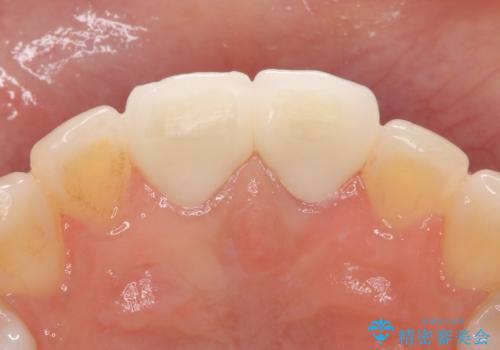

オールセラミッククラウン 変色が気になる前歯の治療

- 前歯の変色が気になるのでセラミックによる治療を行いたいといらっしゃった方の症例です。

左上1番目の歯の再根管治療終了後、左右1番目の2歯をオールセラミッククラウンで補綴しました。

前歯の補綴ではオールセラミッククラウンを希望される患者様が多いですが、オールセラミッククラウンの中でも、エコノミー、スタンダード、スペシャル、エクセレントとランクがあります。

その中でも特に審美性が高いのがスペシャル、エクセレントです。スペシャル、エクセレントは口腔内写真をもとに熟練の技工士が、患者様の口腔内に合わせたオーダーメイドのクラウンを製作致します。